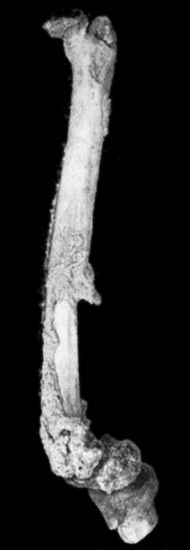

| 118. | Shaft of the Femur after Acute Osteomyelitis | 444 |